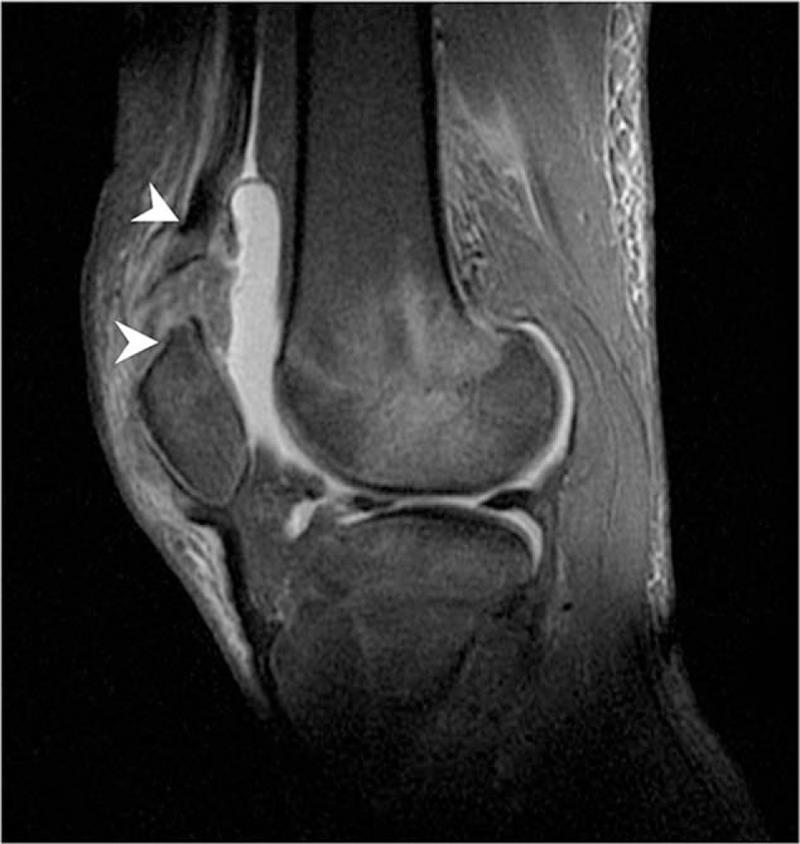

Herein, we report a rare case of a 19-year-old healthy adult female who presented sleeve fracture at the superior pole of the left patella. The clinical and radiological features are found including joint effusion, anterior tilt of the patella and a shell of bone lying proximally to the patella.

Computed tomography and magnetic resonance imaging examination have been performed to further confirm the diagnosis of sleeve fracture, rupture of the quadriceps tendon and the cartilaginous injury.

在此,我们报告一例罕见病例,一名19岁健康成年女性,左髌骨上极出现袖套状骨折。发现其临床和影像学特征包括关节积液、髌骨前倾以及位于髌骨近端的骨壳。

已进行计算机断层扫描和磁共振成像检查,以进一步确诊袖套状骨折、股四头肌肌腱断裂和软骨损伤。